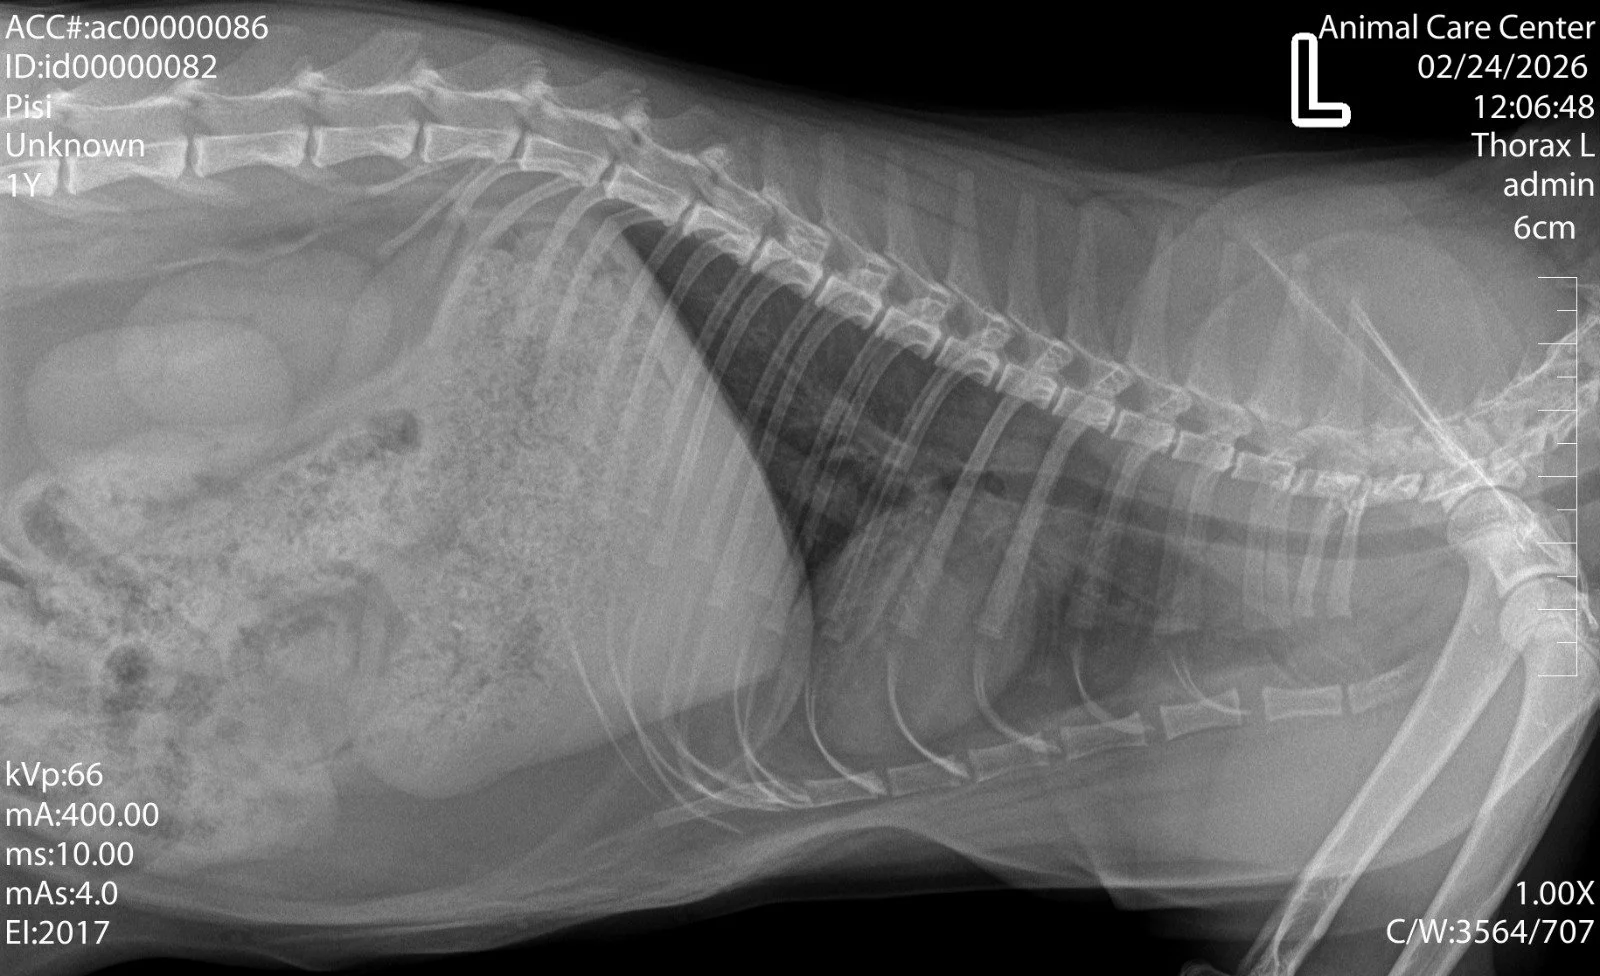

3.3. Afecțiuni toracice

Pentru afecțiunile toracice, radiografia permite evaluarea plămânilor și a inimii, fiind utilă în diagnosticarea bolilor pulmonare, a problemelor cardiace sau a prezenței lichidului în cavitatea toracică.